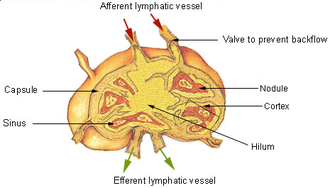

Limfni čvorovi (lymphonodi, nodi lymphatici) su limforetikulski organi uključeni u tok limfe, smješteni posvuda po tijelu (osim u središnjem živčanom sustavu), osobito na sjecištima limfnih žila iz pojedinih područja tijela (regionalni limfni čvorovi). Obavijeni su vezivnom čahurom, koja u unutrašnjost šalje razgranjene pretince (trabekule). Prostore između njih ispunjava retikulsko vezivo u kojem su nakupljeni limfociti (limforetikulsko tkivo kore i moždine) i kroz koje teče limfa (limfni sinusi).

Kora ima vanjsku zonu (sekundarni limfni čvorići i difuzno limfno tkivo među njima sadrže limfocite B) i unutrašnju (parakortikalnu) zonu (parakorteks, difuzno limfno tkivo koje sadrži limfocite T, zona ovisna o timusu). Moždina (meduča) se neposredno nastavlja na koru u obliku razgranjenih i međusobno povezanih moždinskih (medularnih) tračaka (difuzno limfno tkivo, sadrži limfocite B).

Limfni sinusi su široki, nepravilni prostori (usporen protok limfe povoljan za izmjenu limfocita i fagocitnu aktivnost), nepotpuno obloženi spljoštenim retikulskim (litoralnim) stanicama. Njihov lumen je premošćen retikulskim stanicama (sposobnost fagocitoze) retikulskim vlaknima i makrofagima. Kroz čahuru ulaze u limfni čvor aferentne limfne žile i dovode limfu koja sukcesivno prolazi kroz limfne sinuse smještene između čahure i kore (periferni supkapsularni ili marginalni sinusi), između kore i trabekula (kortikalni, peritrabekularni ili intermedijarni sinusi) i između moždinskih trčaka (moždinski ili medularni sinusi).

U hilusu se svi moždinski sinusi stječu u eferentne limfne žile. Krvne žile ulaze na hilusu, granaju se u trabekulama i moždinskim sinusima i čine kapilarnu mrežu oko zametnih centara limfnih čvorića u kori.